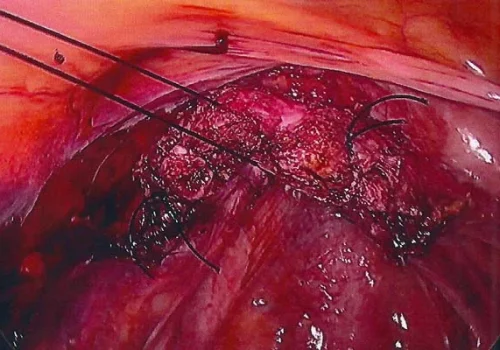

Procedure

She subsequently underwent Total Laparoscopic Hysterectomy and Laparoscopic Mesh Sacral Colposuspension.